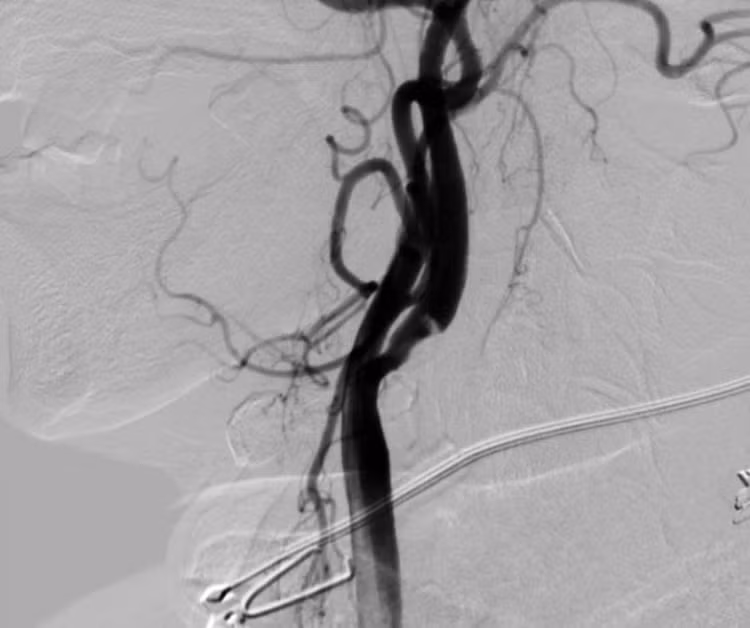

dot-quy-cao-3.jpg

Hình DSA cho thấy hẹp nặng đoạn gốc động mạch cảnh trong ngoài sọ trước can thiệp của bệnh nhân đột quỵ.